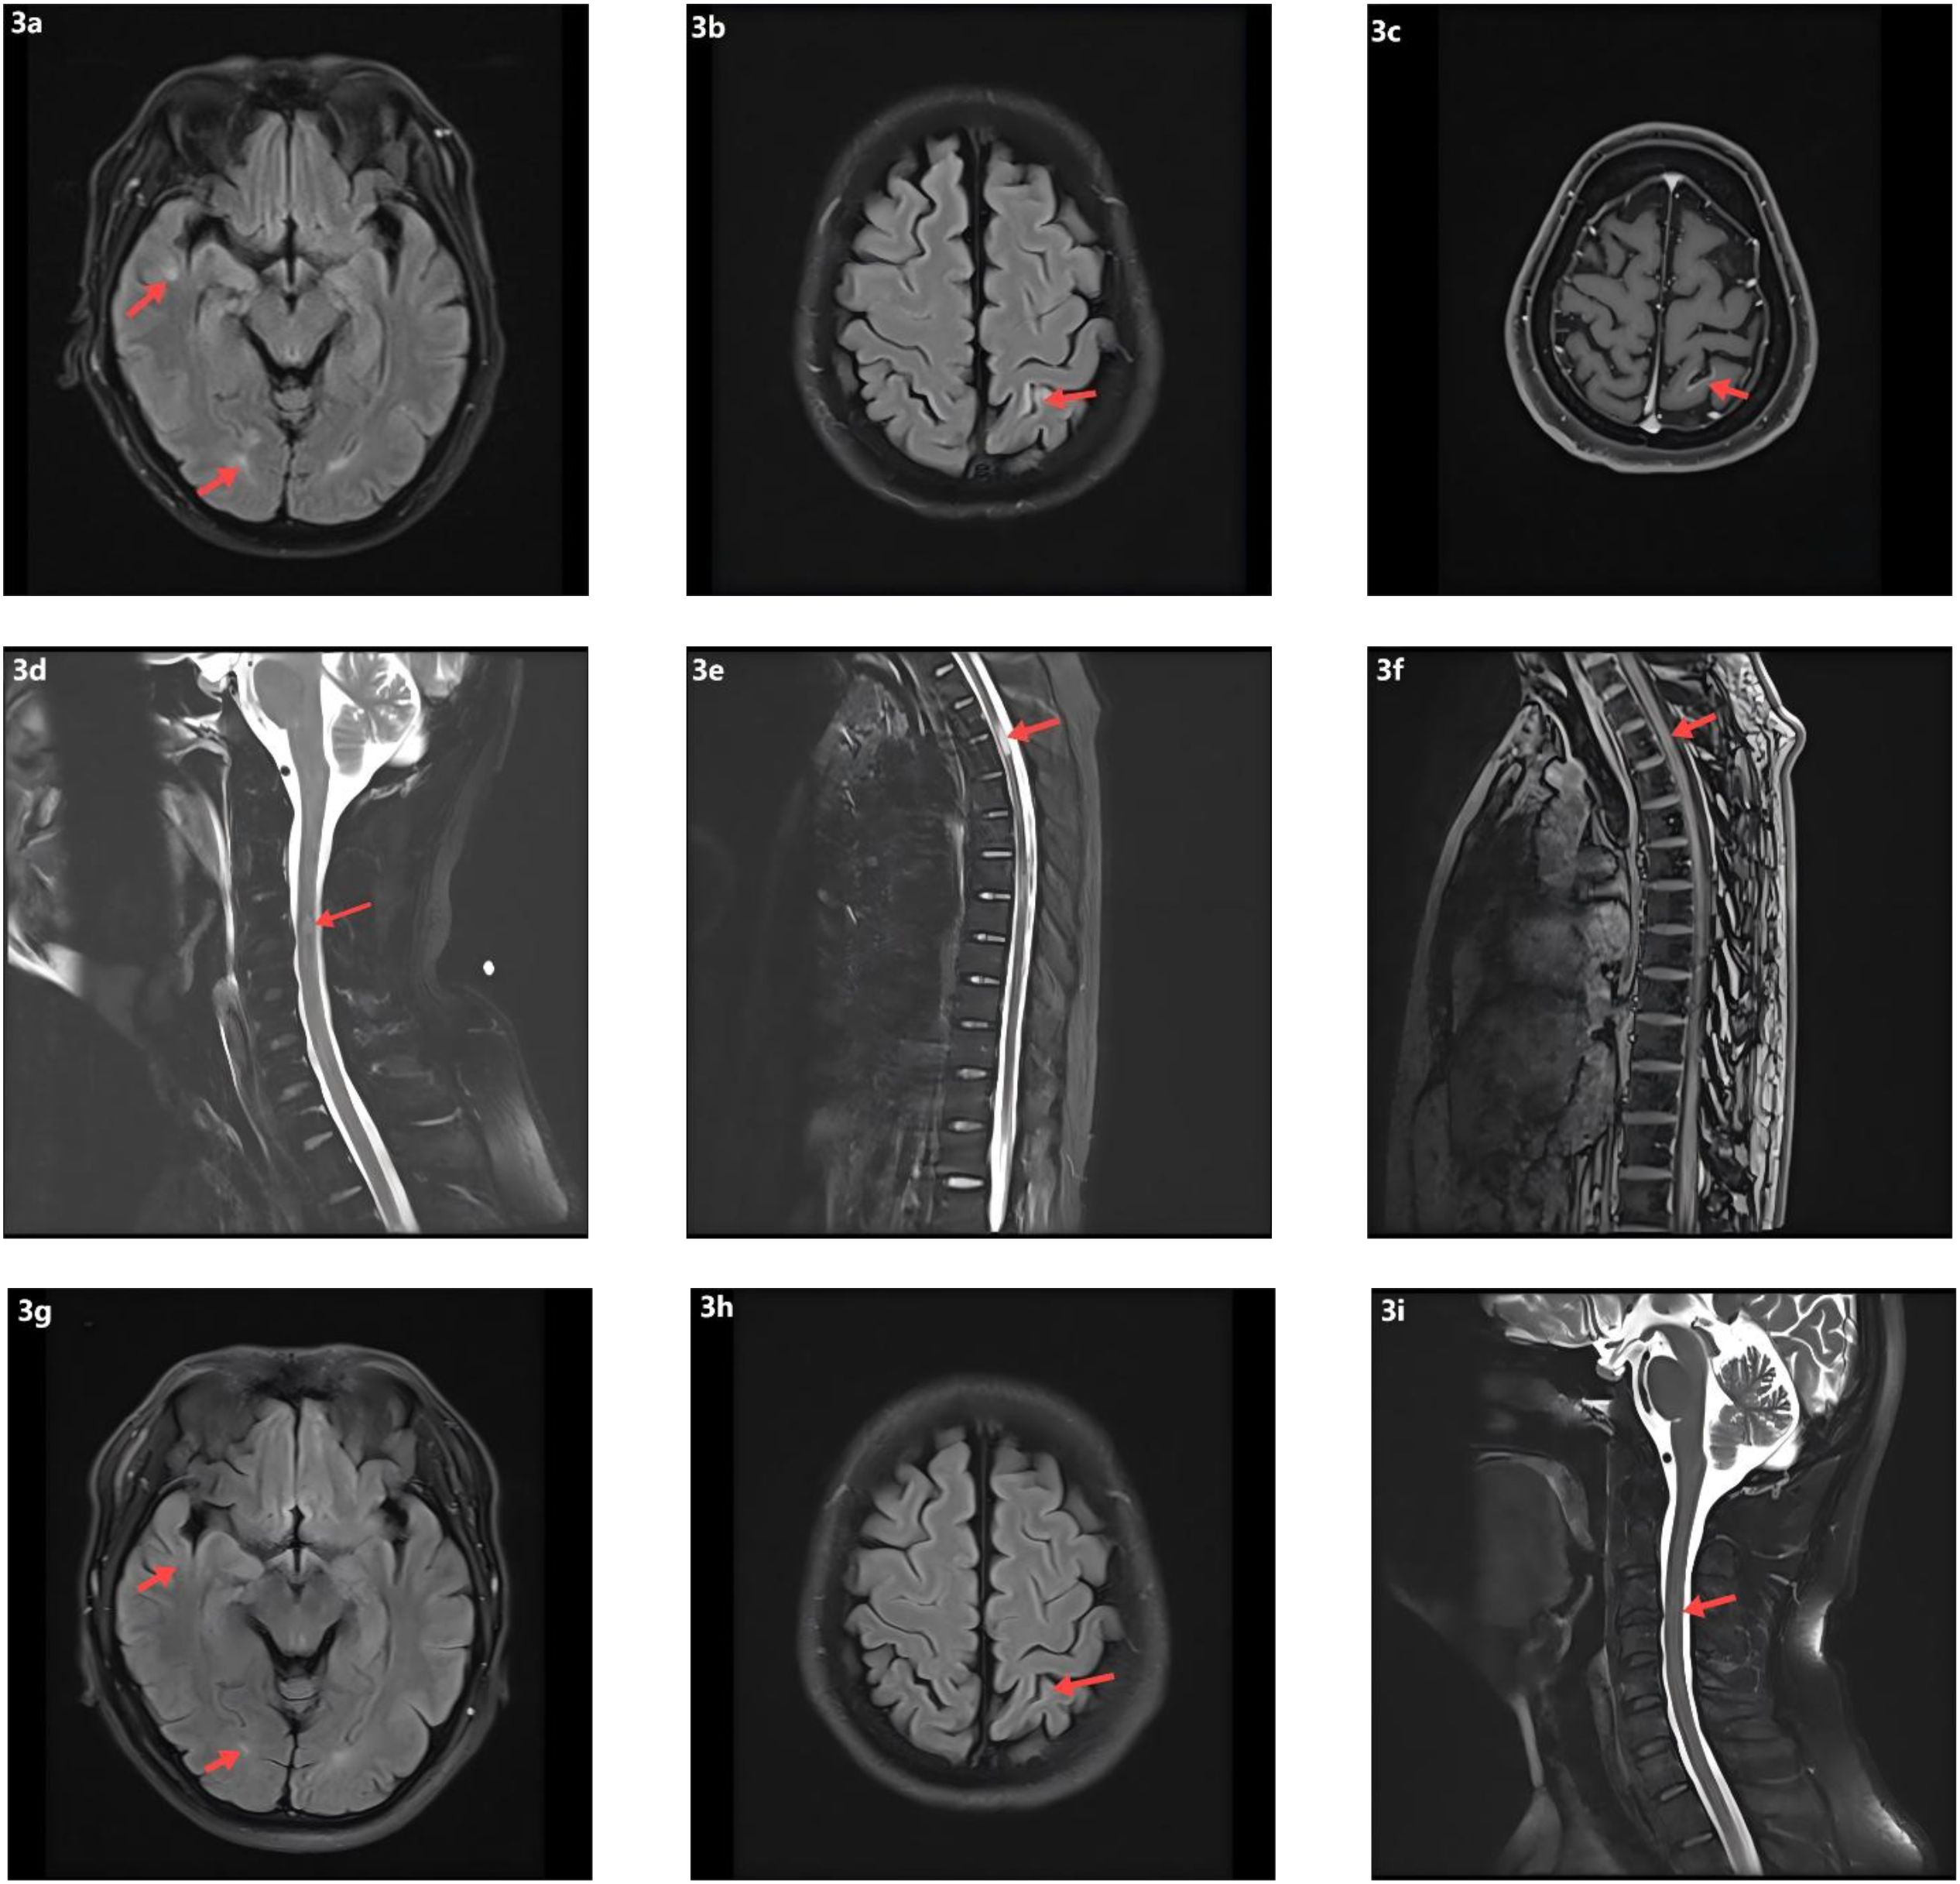

On day 7, the patient abruptly developed severe ventilatory failure (arterial blood gas: pH 6.90, PaCO2 115 mmHg, PaO2 56 mmHg) and was transferred to the intensive care unit for endotracheal intubation and mechanical ventilation. Concurrently, right-sided mydriasis; dysarthria/dysphagia; limb weakness [Medical Research Council (MRC) grades: right upper 2/5, left upper 3/5, both lower limbs 2/5]; absence of deep tendon reflexes in all limbs; negative Babinski and Kernig signs bilaterally; reduced sensation below the T4 level; and nuchal rigidity emerged. Lumbar puncture demonstrated albuminocytologic dissociation (Supplementary Table S4); serum IL-6 was markedly elevated at 178.7 pg/mL; and chest CT showed minimal pulmonary exudative changes. Comprehensive neuroimmunological evaluation demonstrated that Cerebrospinal fluid (CSF) oligoclonal bands were negative; assays for central and peripheral nervous system–related autoantibodies (anti-GQ1b, anti-NF155, anti-AQP4, anti-MOG, anti-MAG; see Supplementary Table S3) were all negative. CSF infectious testing—including metagenomic next-generation sequencing (mNGS)—did not identify a specific pathogen (Supplementary Table S4). On day 9, electrodiagnostic testing revealed multifocal demyelinating changes of the peripheral nerves (Supplementary Table S5), and the initial differential diagnosis included GBS versus NMOSD. Beginning on day 12, high-dose intravenous methylprednisolone (1 g/day for 5 consecutive days) was administered in combination with therapeutic plasma exchange (six sessions; total exchange volume 26 600 mL); however, there was no improvement in neurological or respiratory status (muscle strength unchanged with persistent sensory deficits). On day 16, repeat lumbar puncture showed the opening pressure had decreased to 220 mmH2O, while protein had increased to 0.67 g/L (Supplementary Table S4); the autoimmune encephalitis antibody panel remained negative (Supplementary Table S3). On day 18, intravenous immunoglobulin (IVIG, 0.4 g/kg/day for 5 days) was given, but neurological and respiratory function still did not improve. On day 24, visual evoked potentials indicated central conduction impairment (Supplementary Table S6); brain MRI demonstrated scattered cortical T2/FLAIR hyperintensities in the right temporal and bilateral frontoparietal regions with mild leptomeningeal enhancement in the left frontoparietal area (Figures 3a–c), while cervical/thoracic spinal MRI showed central canal–adjacent T2 hyperintensities at C3 and T3–T4 with mild enhancement (Figures 3d–f). Integrating the imaging and neurophysiological findings with the clinical phenotype and prior literature (2, 3, 7), a final diagnosis of CCPD was established.

Figure 3. Neuroimaging findings and follow-up MRI. (a) Scattered punctate T2-weighted and FLAIR hyperintense lesions in the right temporal and frontoparietal lobes. (b) Similar scattered hyperintense lesions in the left frontoparietal cortex on T2-weighted and FLAIR sequences. (c) Post-contrast T1-weighted imaging shows focal leptomeningeal enhancement in the left frontoparietal region. (d) T2 hyperintensity surrounding the central canal at the C3 level of the cervical spinal cord. (e) T2 hyperintensity around the central canal at the T3–T4 levels of the thoracic spinal cord. (f) Mild contrast enhancement of the T3–T4 spinal cord lesions on post-contrast T1-weighted images. (g) Follow-up T2-FLAIR images demonstrate resolution of the hyperintense lesions in the right temporal and frontoparietal lobes. (h) Decreased FLAIR hyperintensity in the left parietal lobe on follow-up imaging. (i) Resolution of previously abnormal T2 signal in the cervical spinal cord.

At the time of discharge on day 45, the patient had regained muscle strength to MRC grade 4+ in all four limbs, with deep tendon reflexes normalized. However, diminished sensation below the T4 level and mild blurred vision in the right eye persisted. Oral prednisone acetate (60 mg/day) was prescribed at discharge and tapered by 5 mg per week until discontinuation. At the follow-up visit on day 136, muscle strength had fully recovered, although mild visual blurring in the right eye remained. Repeat MRI showed near-complete resolution of the brain parenchymal lesions and complete disappearance of abnormal cervical spinal cord signals (Figures 3g–i). The patient declined further neurophysiological testing. At the 18-month follow-up, the only residual symptom was mild blurring of vision in the right eye, and no relapses had occurred. In view of the rapid and durable remission achieved with low-dose RTX, we adopted an observation-first management strategy without scheduled maintenance therapy; re-treatment would be triggered by CD19+ B-cell reconstitution—monitored by flow cytometry when feasible—or by new clinical or MRI evidence of disease activity. Notably, the patient declined flow-cytometric monitoring during follow-up.